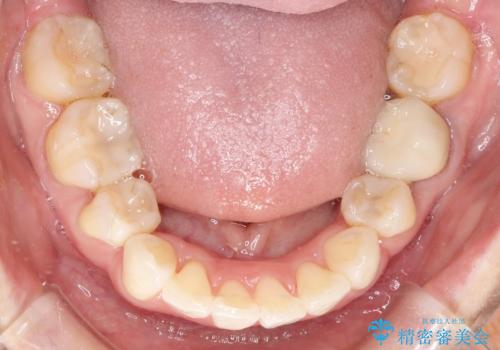

- 上下の歯のがたつきを主訴に来院されました。

上下の前歯の叢生とかみ合わせが深い過蓋咬合という状態でした。

上下左右の歯を1本ずつ抜歯して、ワイヤーにて矯正を行いました。

かみ合わせの深さを改善するのに時間がかかり、予定よりも治療期間が長期化しましたが、整った歯並びへ改善することができました。